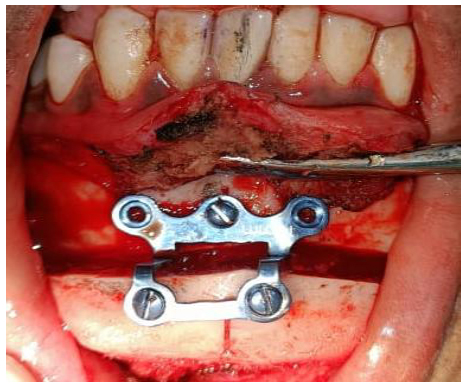

Markings for Advancement genioplasty were given over the lower labial mucosa. Advancement genioplasty with symmetry correction was performed to coincide with the dental and skeletal midline. A genioplasty plate of size 2 mm with five screws (2 mm × 10 mm each) was placed. A Romovac drain was placed over the left preauricular region. Closure was done in layers. Intraorally, the muscle and mucosa were sutured with 3-0 Vicryl, and extraorally, the muscle layer was sutured with 3-0 Vicryl and the skin layer with 4-0 Ethilon. Pressure dressing was given over the preauricular and chin region. The patient was advised to perform active mouth opening exercises postoperatively using a Hister jaw opener. The patient was discharged on postoperative day 10 with a mouth opening of approximately 18 mm (Figs. 4A-D and 5, respectively).

Advancement genioplasty and plating.

CT scans A. Coronal view, B. 3DCT.